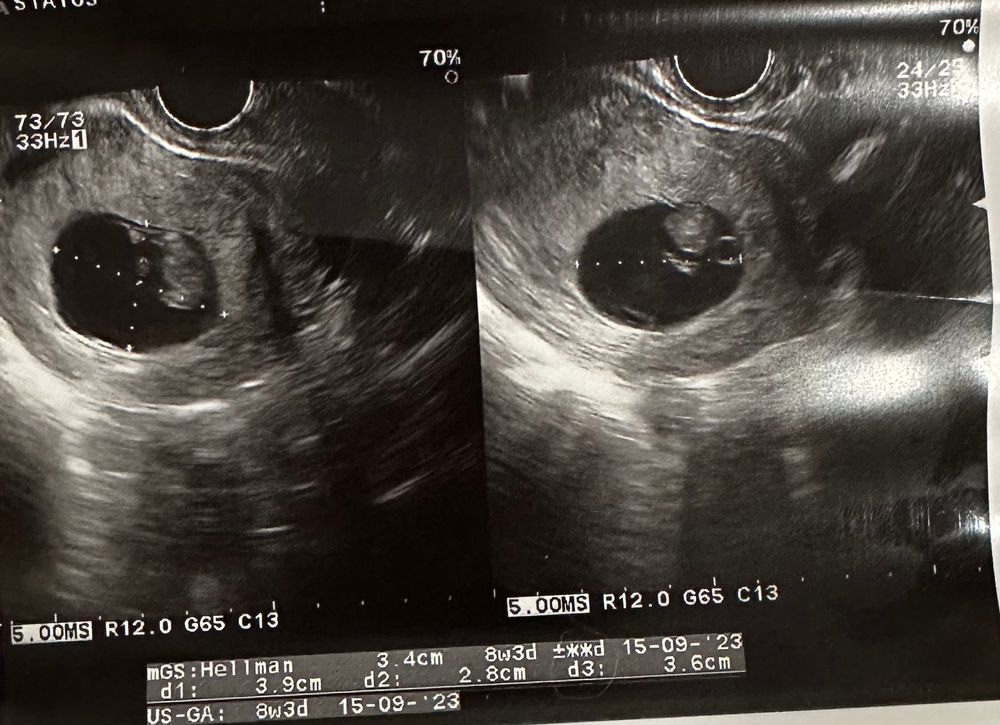

Сходила на Узи…9нед 1день

КТР27 мм, соответствует сроку 9нед 4дня

а вот в этот раз посчитали не диаметр ПЯ, а СВД. На прошлом узи и на этом очетливо видно, что ПЯ не деформировано, но немного уплощено! Нигде не нашла про это информации

ПЯ получается 3.9*2.8*3.6, из-за этого среднее получается каким-то маленьким всего 3.43

если из этого среднего вычесть КТР- свободного места для малыша остаётся 7мм

Вот СВД мерили-он аж на срок 8нед3дня только тянет. А просто диаметр 39мм(прошлое узи 27мм)-то есть за 12 дней выросло ровно на 12мм